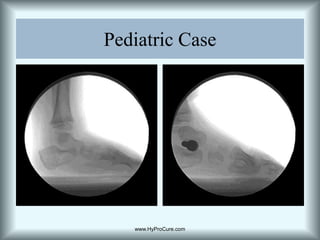

Repositioning of the talus on the tarsal mechanism.HyProCure stabilizes the talus to prevent anterior dislocation. Maintains the articular facets, keeps the sinus open.www.HyProCure.com

Talar declination decreased and brought back to normal alignment.HyProCure  restores talar position on the tarsal mechanism.www.HyProCure.com

Navicular DropThe navicular is forced out of position due to the excessive abnormal forces from the talar displacement.  Stabilization of the talus internally prevents navicular drop. www.HyProCure.com

What is wrong with this picture.Plantarflexed talusAnterior deviation of cymaNavicular dropSustentaculum dropThis is not a “flat” foot look at the calcaneal inclination angle.Talotarsal subluxationwww.HyProCure.com